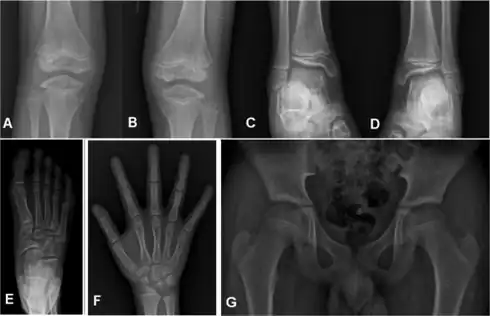

Children with autosomal dominant MED experience joint pain and fatigue after exercising. Their x-rays show small and irregular ossifications centers, most apparent in the hips and knees. There are very small capital femoral epiphyses and hypoplastic, poorly formed acetabular roofs.[1] A waddling gait may develop. Knees have metaphyseal widening and irregularity while hands have brachydactyly (short fingers) and proximal metacarpal rounding. Flat feet are very common.[2] The spine is normal but may have a few irregularities, such as scoliosis.

By adulthood, people with MED are of short stature or in the low range of normal and have short limbs relative to their trunks. Frequently, movement becomes limited at the major joints, especially at the elbows and hips. However, loose knee and finger joints can occur. Signs of osteoarthritis usually begin in early adulthood.[3]

Children with recessive MED experience joint pain, particularly of the hips and knees, and commonly have deformities of the hands, feet, knees, or vertebral column (like scoliosis). Approximately 50% of affected children have abnormal findings at birth (such as club foot or twisted metatarsals, cleft palate, inward curving fingers due to underdeveloped bones and brachydactyly, or ear swelling caused by injury during birth). Height is in the normal range before puberty. As adults, people with recessive MED are only slightly more diminished in stature, but within the normal range. Lateral knee radiography can show multi-layered patellae.[3]